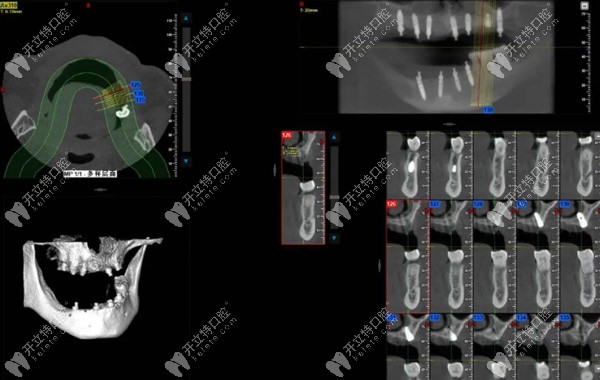

院長(zhǎng)進(jìn)一步根據(jù)術(shù)前檢查,用雅悅的“AI數(shù)字化一站式定制中心”的CBCT設(shè)備獲取口腔數(shù)據(jù)進(jìn)行分析。

牙齒缺損位置:15,14,12,11,12,13,14,17,部分牙齒松動(dòng),46可用骨高度大于13mm,骨寬度7-9mm,其余骨高度、寬度尚可。

梁先生術(shù)后ct▲